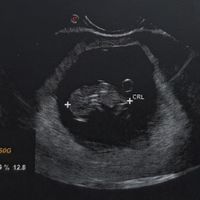

Ciao a tutte! Quante, come me, hanno appena scoperto di essere in attesa? Come state vivendo questo periodo? Raccontiamoci... Secondo i miei calcoli, dovrei avere la scadenza il 1 Agosto, ma credo che...

Ciao a tutte! Quante, come me, hanno appena scoperto di essere in attesa? Come state vivendo questo periodo? Raccontiamoci... Secondo i miei calcoli, dovrei avere la scadenza il 1 Agosto, ma credo che la ginecologa, alla prima ecografia, mi...